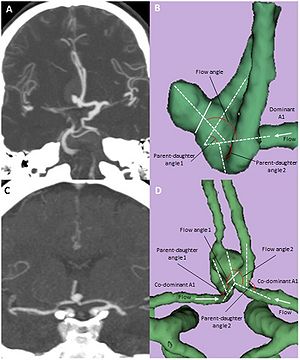

MRI example of white matter lesions and the segmented deep grey matter structures. Lesions and anatomical regions of interest are illustrated on a set of MR images from a 53 year-old male MS patient. Left – axial FLAIR; right – axial diffusivity map. The output of computer-assisted segmentation of the lesions is shown on FLAIR. The 3D models of the manually outlined caudate (green), putamen (blue) and thalamus (red) are overlaid on the fractional anisotropy map of a single section containing these structures. The putamen and the thalamus was manually outlined on AD maps using 3D Slicer (www.slicer.org) |